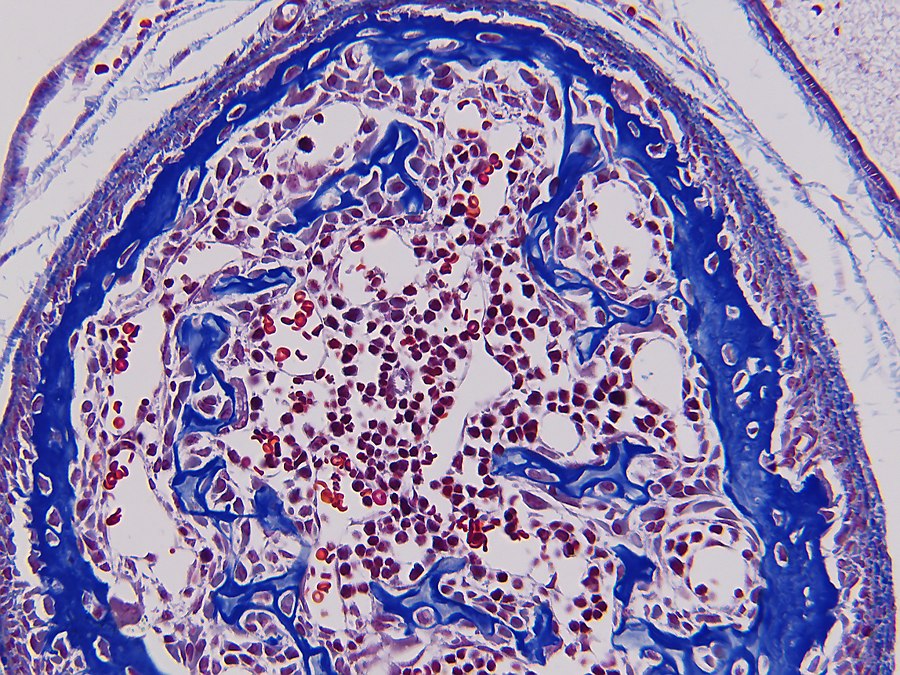

Bone formation or ossification[2] visualized by various histological stains.

In both cases, primary (braided or plexiform) bone is first formed, which is soon replaced by secondary (lamellar) bone, which may have a compact or spongy appearance macroscopically. During bone growth, areas of primary bone, bone breakdown, and secondary bone continually occur side by side. This coexistence of breakdown and creation (remodeling) continues in the adult body, although at a much slower rate.

Bone is composed of cells and intercellular material that is calcified, the bone or bone matrix. Three types of cells can be distinguished:

1. Osteoblasts (bone forming cells), which produce the organic components of the bone matrix. Osteoblasts arise from osteoprogenitor cells, which are found in endosteum[2] and periosteum[2]. Osteoblasts synthesize the organic components of the bone matrix and thus produce collagen type I, proteoglycans[2] and glycoproteins[2]. Osteoblasts are located in contiguous rows, the osteoblast hemisphere, against the surface of the bone;

2. Osteocytes (mature bone cells) formed by maturation of osteoblasts lie in cavities (lacunae) of the bone matrix. From these cavities, canaliculi run through the bone in different directions, containing the outgrowths of osteocytes. They make contact with each other through gap junctions[2], allowing the exchange of ions and small molecules;

3. Osteoclasts (bone-degrading cells); these are large multinucleated (up to fifty nuclei) cells that can break down bone. Osteoclasts are freely motile cells and lie as elongated cells against the bone margin, sometimes in a hollow created by them eating away matrix: the lacuna of Howship.